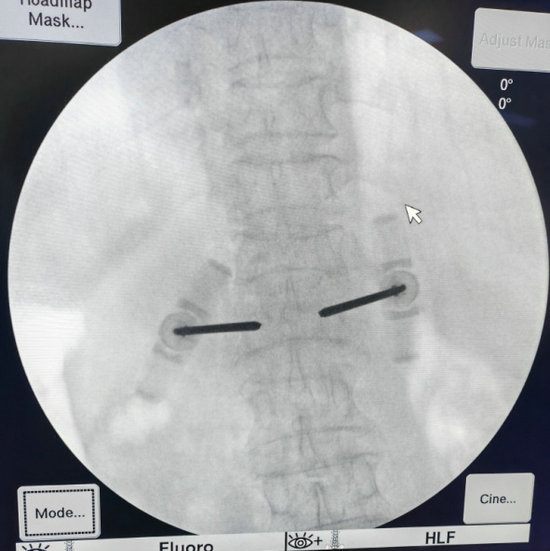

经皮穿刺椎体骨水泥成形术是一项在局麻下即可完成的手术,仅需要在背部伤椎相对应的位置切2个1cm左右的小口,然后将穿刺针穿刺到椎体前1/3的深度。

在透视确认位置良好后,即可注入骨水泥,待确认骨水泥完全凝固后,去除穿刺针,包扎伤口,手术就结束了。